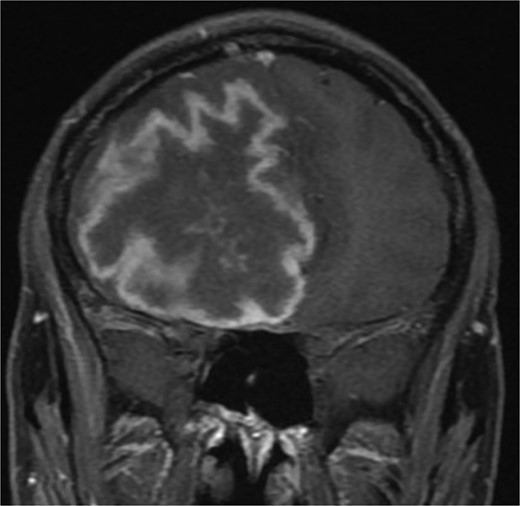

One year later, the patient presented to the emergency department with dizziness, vomiting, and headaches that had started 20 days prior. The CT scan and MRI showed orbital and intracranial invasion. Subsequently, the patient underwent FESS revision with an open craniotomy. The histopathological results revealed findings similar to the first presentation, so the patient was started on intravenous amphotericin B, voriconazole, and dexamethasone. The patient was stable postoperatively until 2 months when he began to deteriorate, and a brain MRI revealed a cerebral abscess (Fig. 4). The patient underwent an urgent open craniotomy with drainage and was shifted to the intensive care unit. However, his condition continued to worsen, and he passed away after 1 month.

Brain MRI showing right-sided cerebral abscess with midline shift to the left side.